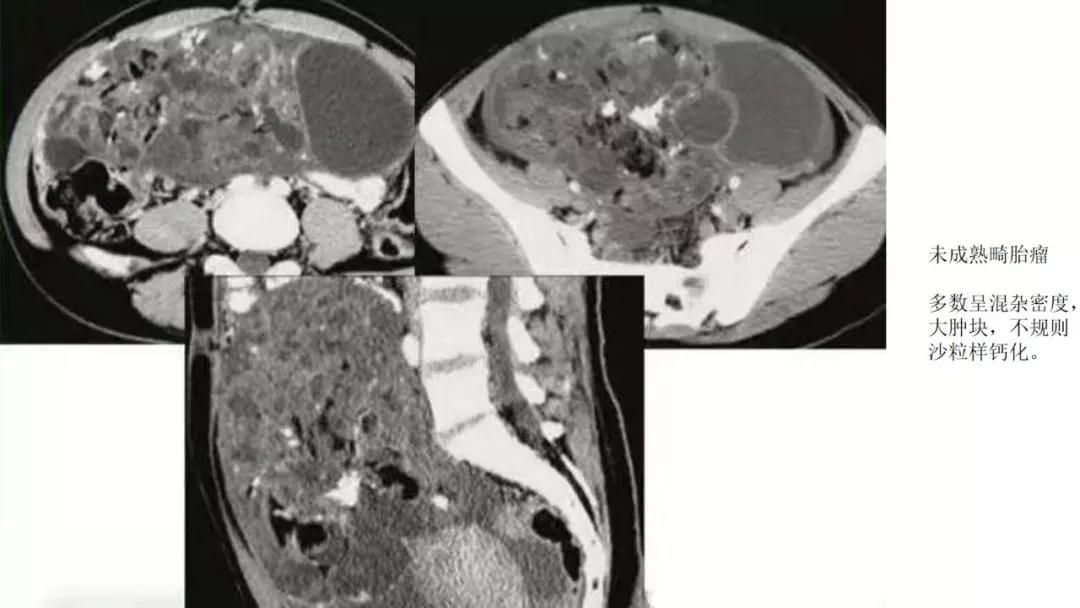

恶性者常呈实性或混杂性肿块,多数边界清楚,可伴有不规则沙粒状钙化。无性细胞瘤常为实性肿块,轻度强化,内胚窦瘤实性成分明显强化,不成熟畸胎瘤呈混杂密度。结合年龄及临床生化检查,有助于诊断。

出现脂肪:畸胎瘤,囊性为主是成熟、实性为主是不成熟